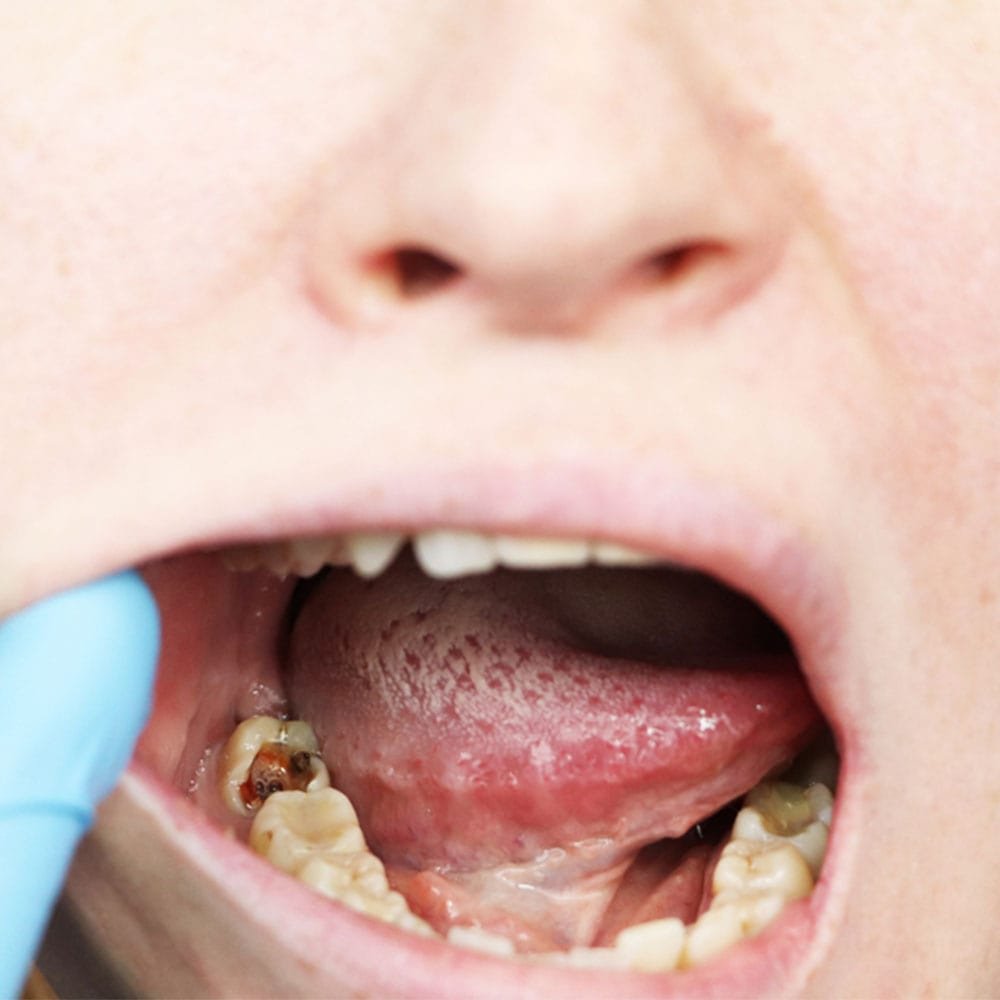

carie dentaire

Protégez vos dents et luttez contre la carie grâce à des soins complets.